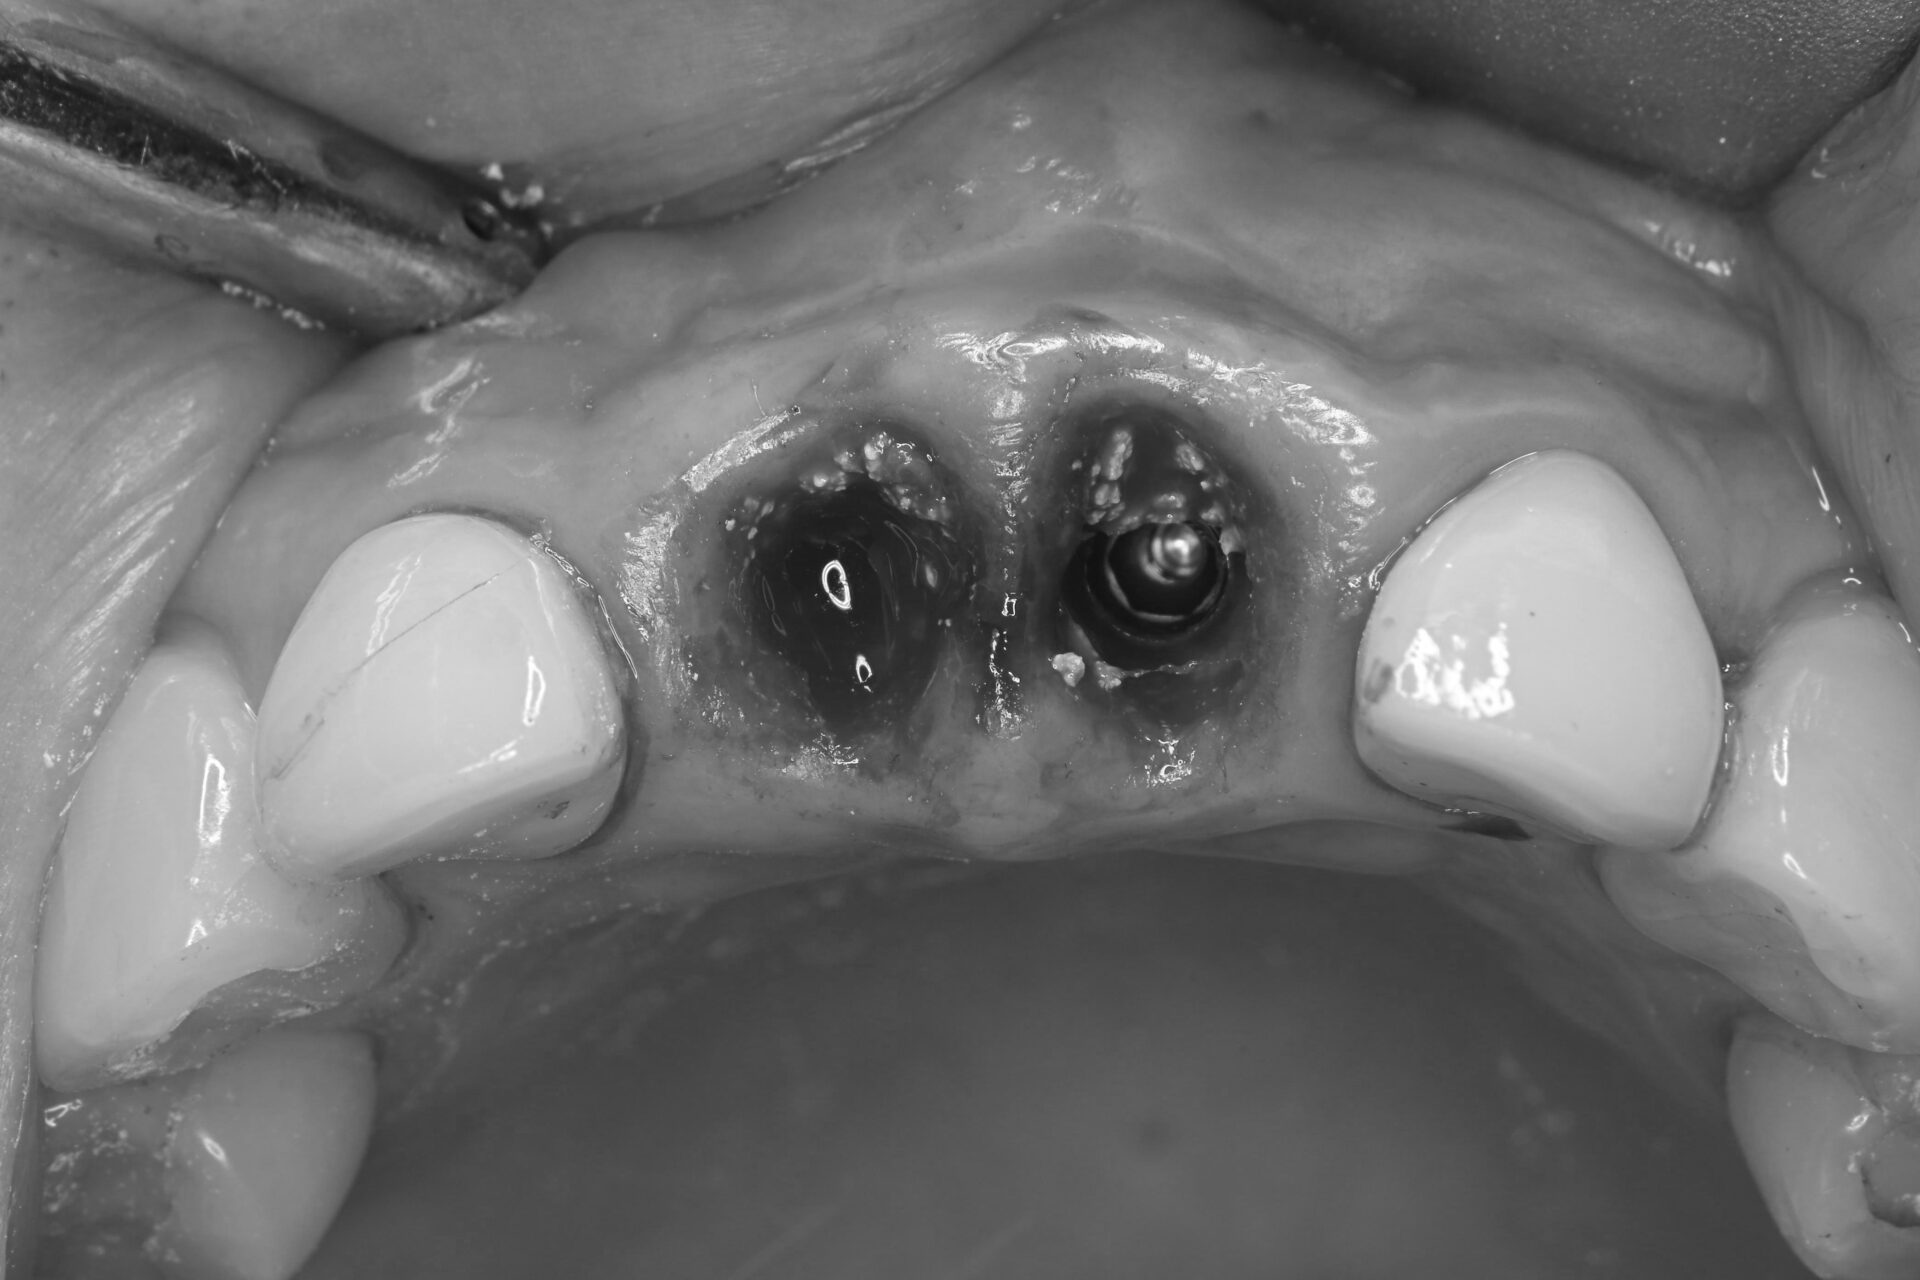

プロビジョナルレストレーションの装着

インプラント体を埋入したその日のうちに仮歯を装着。審美性を確保すると同時に、歯肉の形態を整える役割も担います。患者さんは治療当日から自然な見た目と会話・咀嚼機能を取り戻すことができました。